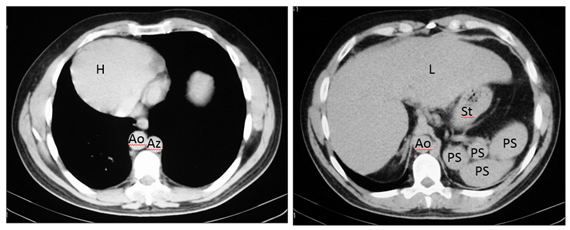

Figure 3 Axial CT images show dextrocardia and cardiac apex on the right (H), the aorta on the right (Ao), azygos vein on the left (Az), liver is midline (L) but slightly on the right and polysplenia (PS) on the left relative to greater curvature of the stomach (St). IVC cannot be identified.